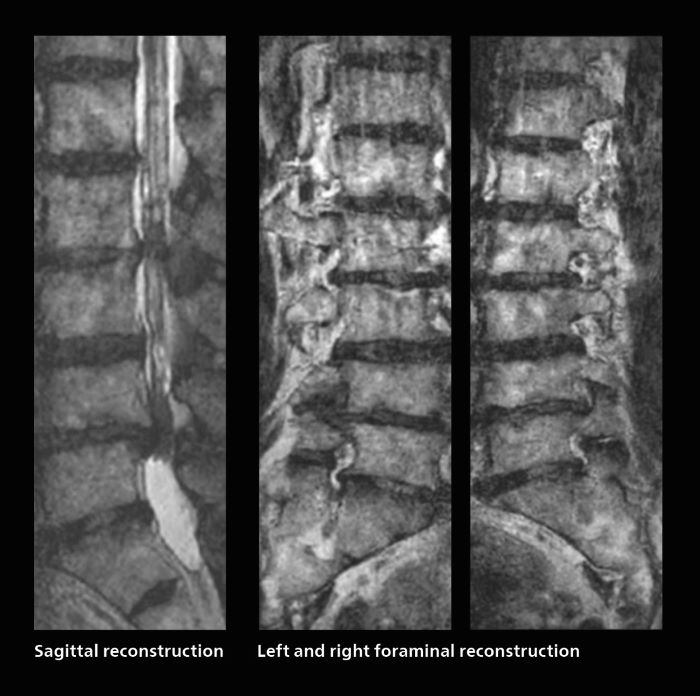

Fast lumbar spine imaging for successful exam of patient in pain

A patient arrived saying that undergoing MRI was not possible because of severe back pain and leg pain, was imaged with SmartSpeed in only 94 seconds. The scan was diagnostic and afterwards the patient confirmed that it only took a little while. Performed on Elition X.

Fast lumbar spine MRI with SmartSpeed of a patient in pain produced a successful isotropic diagnostic scan in only 94 minutes.

The hospital’s fast lumbar spine ExamCard includes T2W SpineVIEW, 1:40 min, 1.0 mm isotropic, acceleration factor 12.